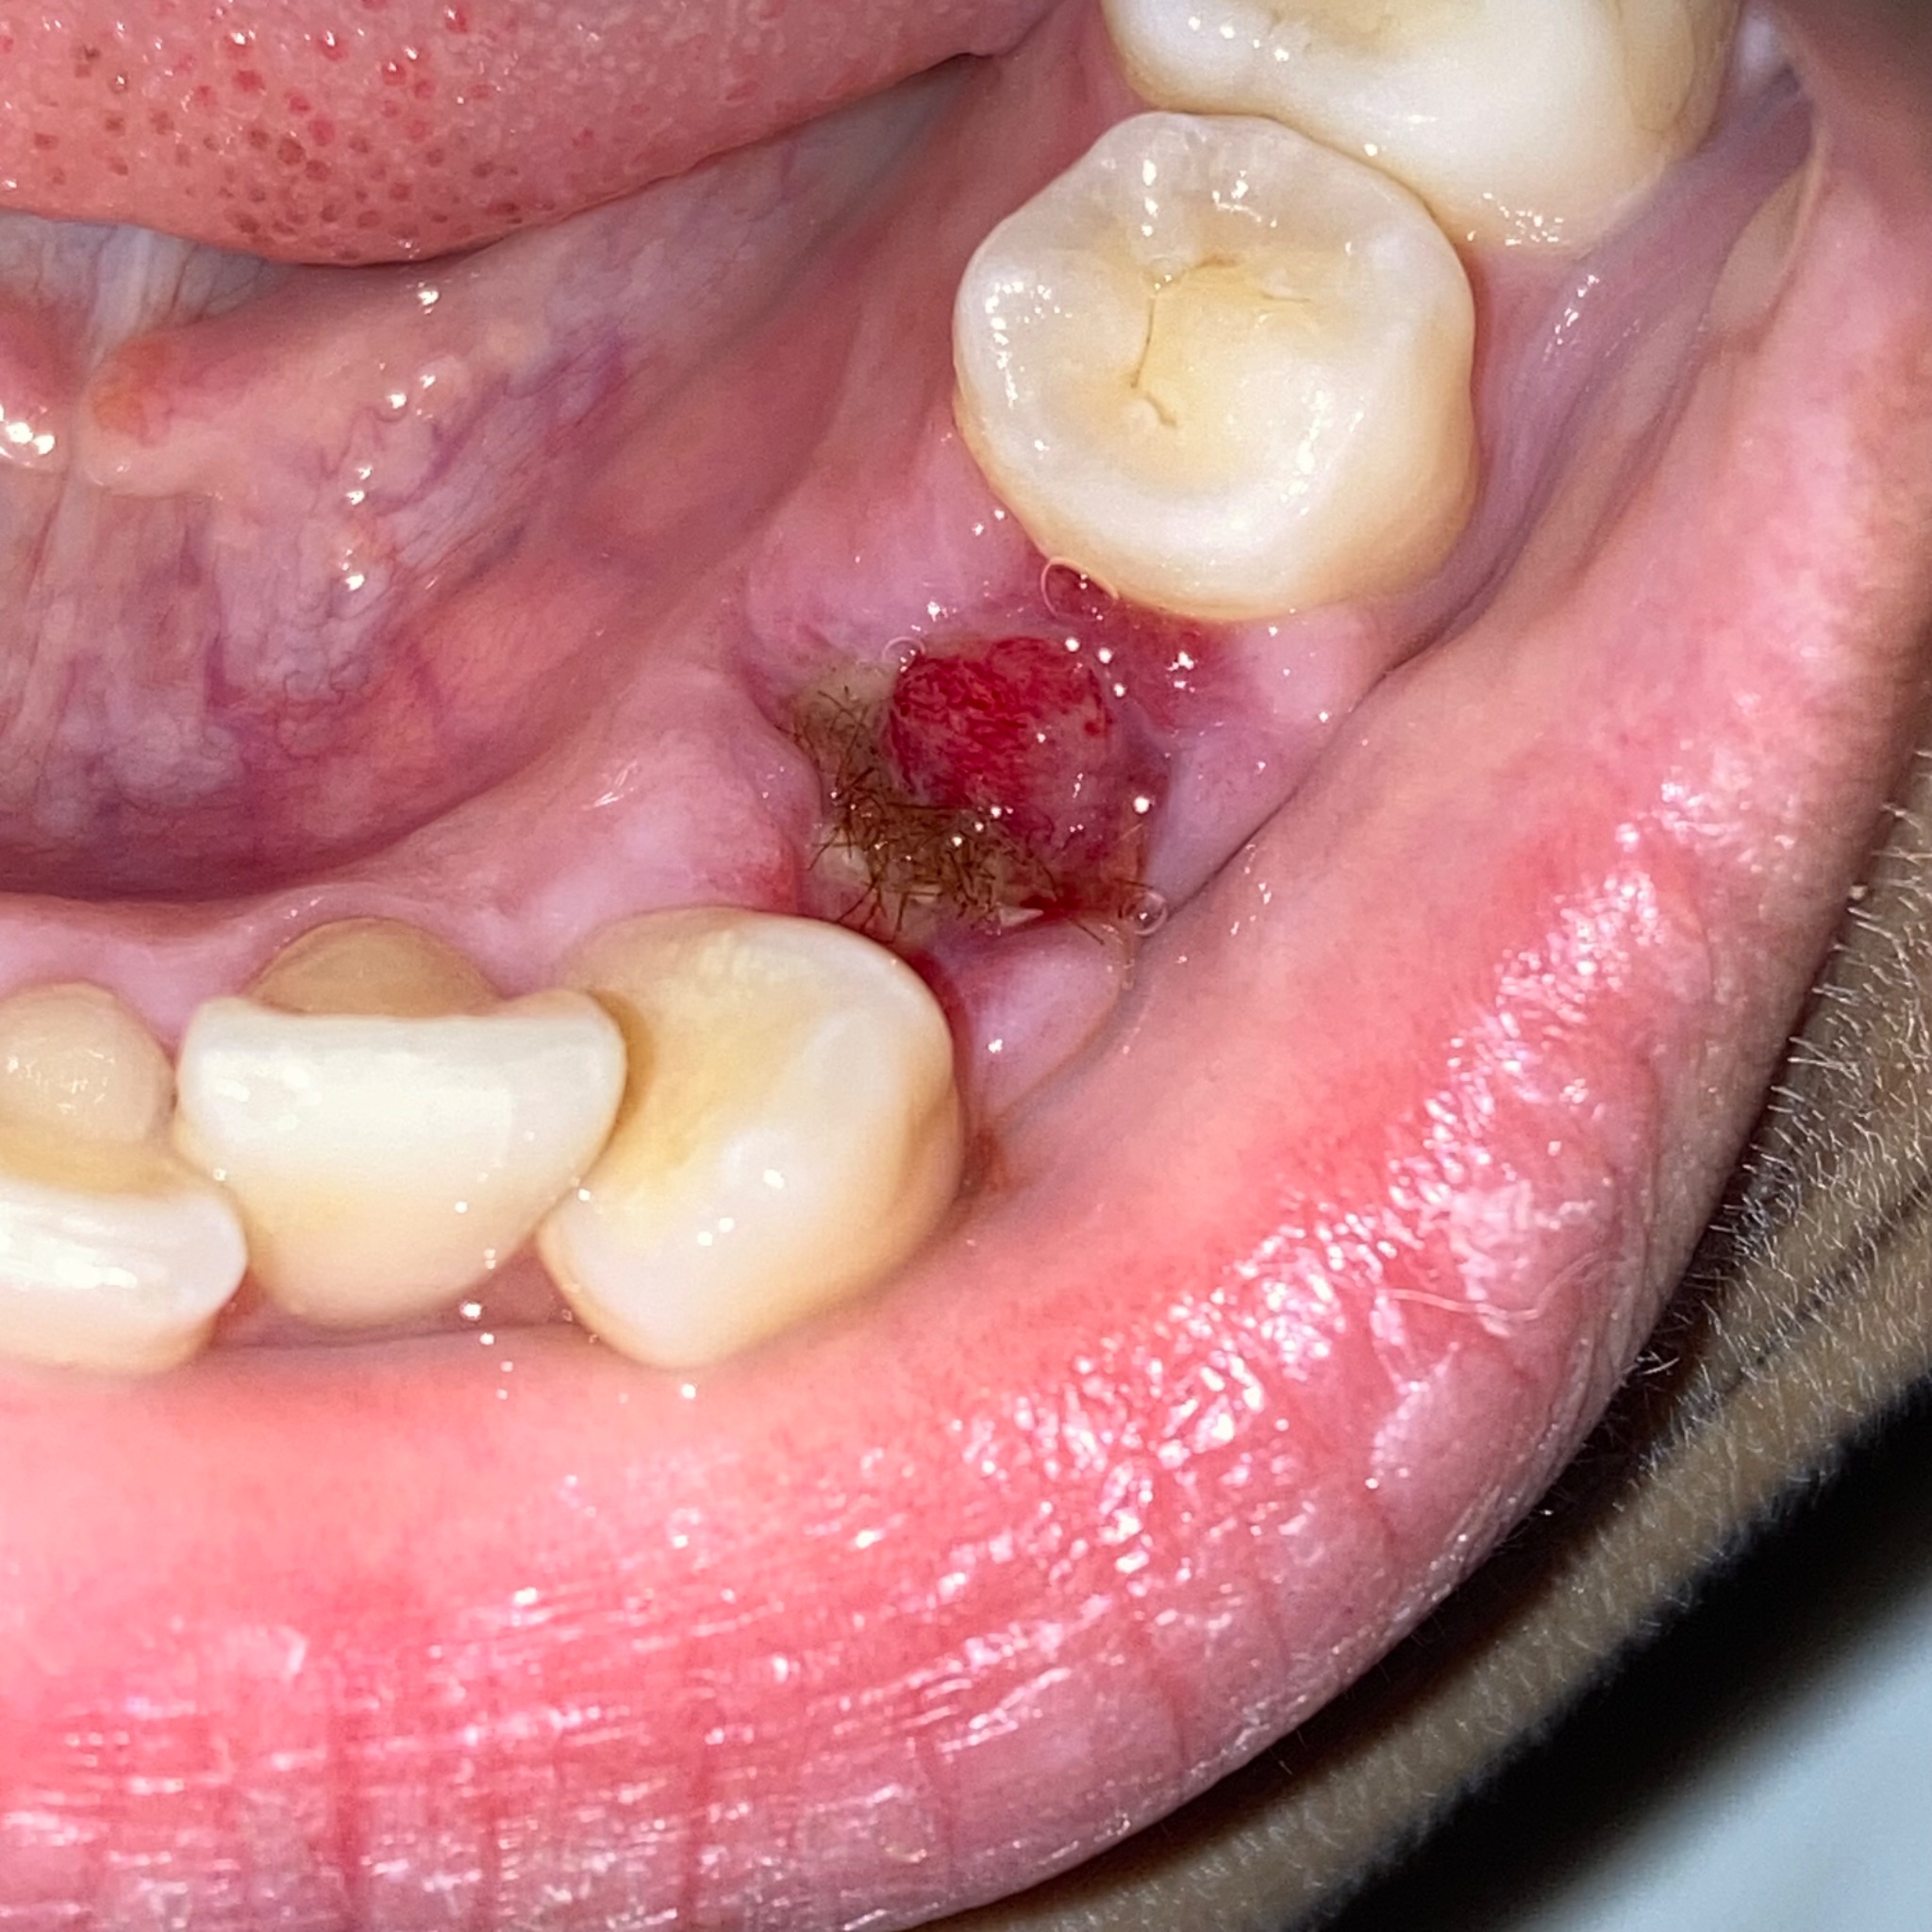

รูปแรกคือวันที่ไปหาหมอแล้วหมอบอกเป็น Dry socket ให้ยาไอบูโพรเฟนกับใส่ยาแก้ปวดในแผลให้ นัดเปลี่ยนยาวันเว้นวัน

เมื่อวานไปใส่ยา บอกหมอว่าไม่ปวดแผลแล้วแต่รู้สึกปวด ๆ แถวเหงือก หมอก็ไม่ว่าอะไร พอกลับบ้านมายาดันหลุด แล้วเห็นตุ่มแดง ๆ เล็ก ๆ (รูป 2 ) นึกว่าเหงือก

ตุ่มแดง ๆ ในแผลถอนฟัน